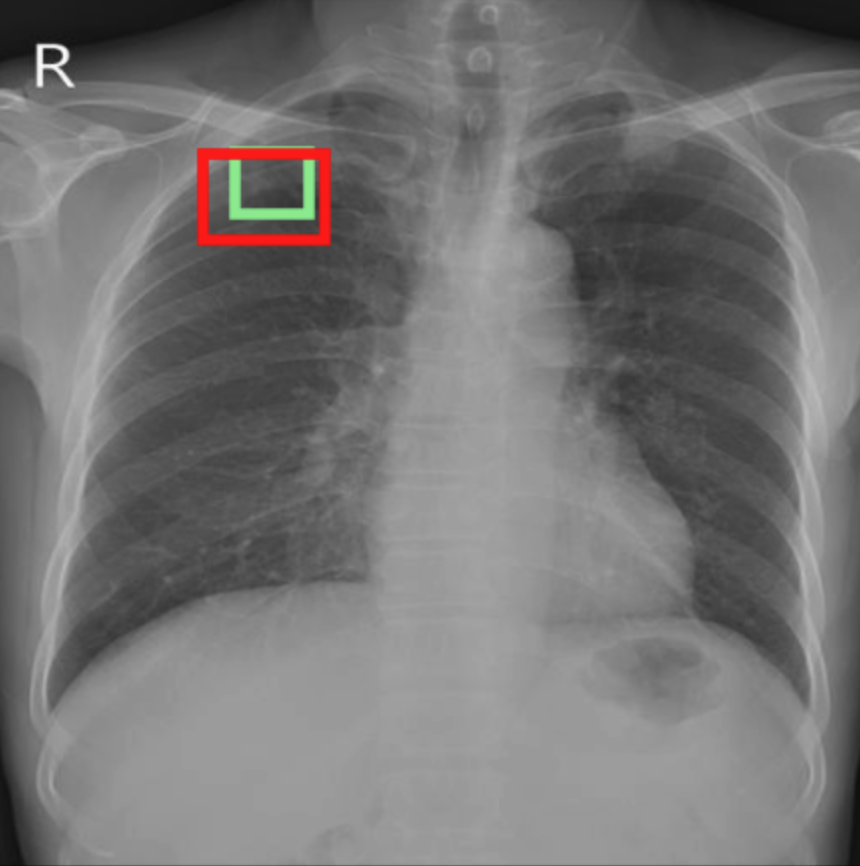

4.3.3 Visual grounding

In this section, we evaluate RadVLM’s visual grounding capabilities, which could help clinicians localize specific regions or pathologies on a CXR. This is particularly useful once a pathology has already been identified – either by a radiologist’s input or through our previously described AI tasks – since it allows one to pinpoint exactly where the abnormality appears on the image.

We report performance metrics for the three main grounding tasks RadVLM was trained on: anatomical grounding using the Chest Imagenome test set, abnormality grounding using the VinDr-CXR test set, and phrase grounding using the MS-CXR test set (Table 1). For each task, we use mean Average Precision (mAP) as our primary evaluation metric.

As mentioned in Table 2, some of the CXR-specific VLMs already have grounding capabilities. CheXagent was trained to handle both abnormality and phrase grounding tasks, while MAIRA-2 – originally trained to produce radiology reports with grounded observations – is also capable of predicting bounding box coordinates when provided with input text. After retrieving each model’s instruction template for generating bounding box coordinates (Appendix 1-Table 2), we evaluated both CheXagent and MAIRA-2 on all three grounding tasks performed by RadVLM.

Our results show that RadVLM performs well at localizing anatomical regions (e.g., “right lung”, “aortic arch”, illustrated in Figure 5a), achieving a mAP of 85.8 %, by far surpassing the other CXR grounding models (Table 4). This advantage is partly explained by including the Chest Imagenome dataset (and thus the anatomical grounding task) in the training set, which CheXagent and MAIRA-2 did not leverage. However, it remains a key feature for any grounding model to possess a fine-grained understanding of CXR anatomy.

For the abnormality grounding task, RadVLM is less consistent (Figure 5b), likely due to higher sparsity of abnormality locations and labels, yet it still achieves best performance (Table 4). For the phrase grounding task, while MAIRA-2 and CheXagent demonstrate great performance, RadVLM surpasses them with a mAP of 81.8% (Table 4), presumably benefiting from the newly released PadChest-GR dataset (Castro et al.,, 2024) used for training.

Overall, these results show that our instruction tuning strategy for visual grounding (covering three essential tasks), combined to a modern VLM backbone, offers a promising avenue to help clinicians localize anatomical and pathological features during a CXR exam. Furthermore, providing fine-grained details within an LLM-generated output may also enhance the ability to answer grounded questions in a multi-turn setting, as we explore next.

a. Anatomical grounding

silhouette

junction

structures

lung

abdomen

mediastinum

arch

b. Abnormality grounding

thickening

fibrosis

enlargement

lung disease

| Anatomical grounding | Abnormality grounding | Phrase grounding | |

| CheXagent | 6.2 | 26.0 | 69.7 |

| MAIRA-2 | 19.8 | 11.3 | 80.1 |

| RadVLM | 85.8 | 34.6 | 81.8 |